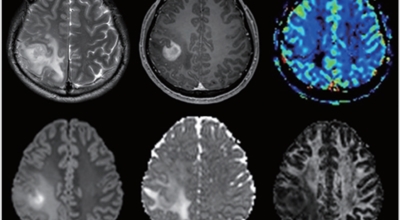

뇌종양이란 뇌 조직이나 뇌를 싸고 있는 막에서 발생한 종양과, 머리뼈나 주변 구조물로부터 멀리 떨어진 부위에서 뇌 조직이나 뇌막으로 전이된 종양을 의미해요. 뇌종양은 양성과 악성으로 나눌 수 있답니다. 양성 뇌종양은 성장 속도가 느리며 주위 조직과의 경계가 뚜렷해요. 양성 뇌종양은 수술 이외의 다른 치료 없이 완치되는 경우가 흔하고, 대부분 천천히 자라기 때문에 수술하지 않고 경과를 관찰하기도 해요.

악성 뇌종양은 뇌암이라고도 하고, 성장 속도가 빠르며 주위 조직으로의 침투 역량이 강해요. 이에 따라 정상 뇌 조직으로 침윤되고 정상 뇌 조직과의 경계가 불분명해서 치료가 어려운 편이예요. 악성 뇌종양은 주변의 정상 뇌 조직을 빠른 속도로 파괴해요.